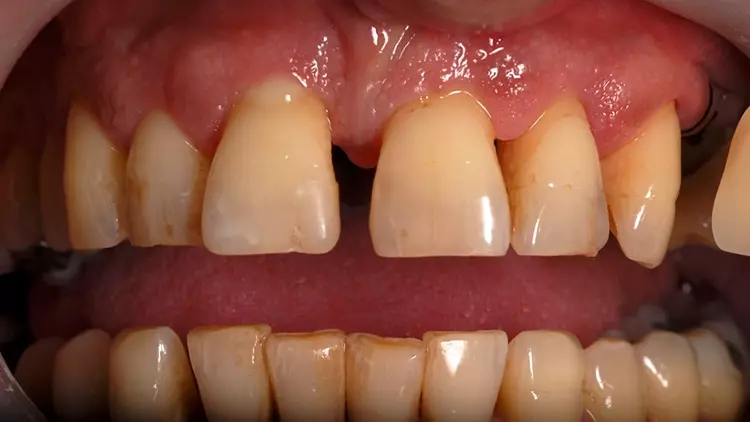

Als Interimsversorgung wurden herausnehmbare, klammerverankerte Prothesen aus Methylmethacrylat verwendet. Nach der dreimonatigen Einheilzeit erfolgten die Implantatfreilegung und die Versorgung mit Einheilkäppchen. Bei der Freilegung der Implantate und der Versorgung mit Einheilkäppchen sowie zum Zeitpunkt der Abformung mit den Abutments in situ lag eine reizlose klinische Situation ohne Anzeichen einer Entzündung im Implantatbereich vor (Abb. 4 und 5).

Nach weiteren vier Wochen wurden PS MultiPlus Abutments (BEGO Implant Systems GmbH & Co. KG) mit einem Platform Shift eingesetzt. Die MultiPlus Abutments wurden nach dem Prinzip „One Abutment, One Time“ direkt am Patienten verschraubt und nicht mehr entfernt. Die Interimsversorgung erfolgte über einen Zeitraum von weiteren zwei Monaten mittels verschraubter Provisorien aus metallverstärktem Komposit (LuxaCrown, DMG-Dental, Hamburg, Deutschland) (Abb. 6 und 7).